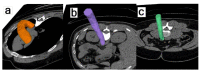

The method of 18F-sodium fluoride (NaF) positron emission tomography/computed tomography (PET/CT) of atherosclerosis was introduced 12 years ago. This approach is particularly interesting because it demonstrates microcalcification as an incipient sign of atherosclerosis before the development of arterial wall macrocalcification detectable by CT. However, this method has not yet found its place in the clinical routine. The more exact association between NaF uptake and future arterial calcification is not fully understood, and it remains unclear to what extent NaF-PET may replace or significantly improve clinical cardiovascular risk scoring. The first 10 years of publications in the field were characterized by heterogeneity at multiple levels, and it is not clear how the method may contribute to triage and management of patients with atherosclerosis, including monitoring effects of anti-atherosclerosis intervention. The present review summarizes findings from the recent 2¾ years including the ability of NaF-PET imaging to assess disease progress and evaluate response to treatment. Despite valuable new information, pertinent questions remain unanswered, not least due to a pronounced lack of standardization within the field and of well-designed long-term studies illuminating the natural history of atherosclerosis and effects of intervention.